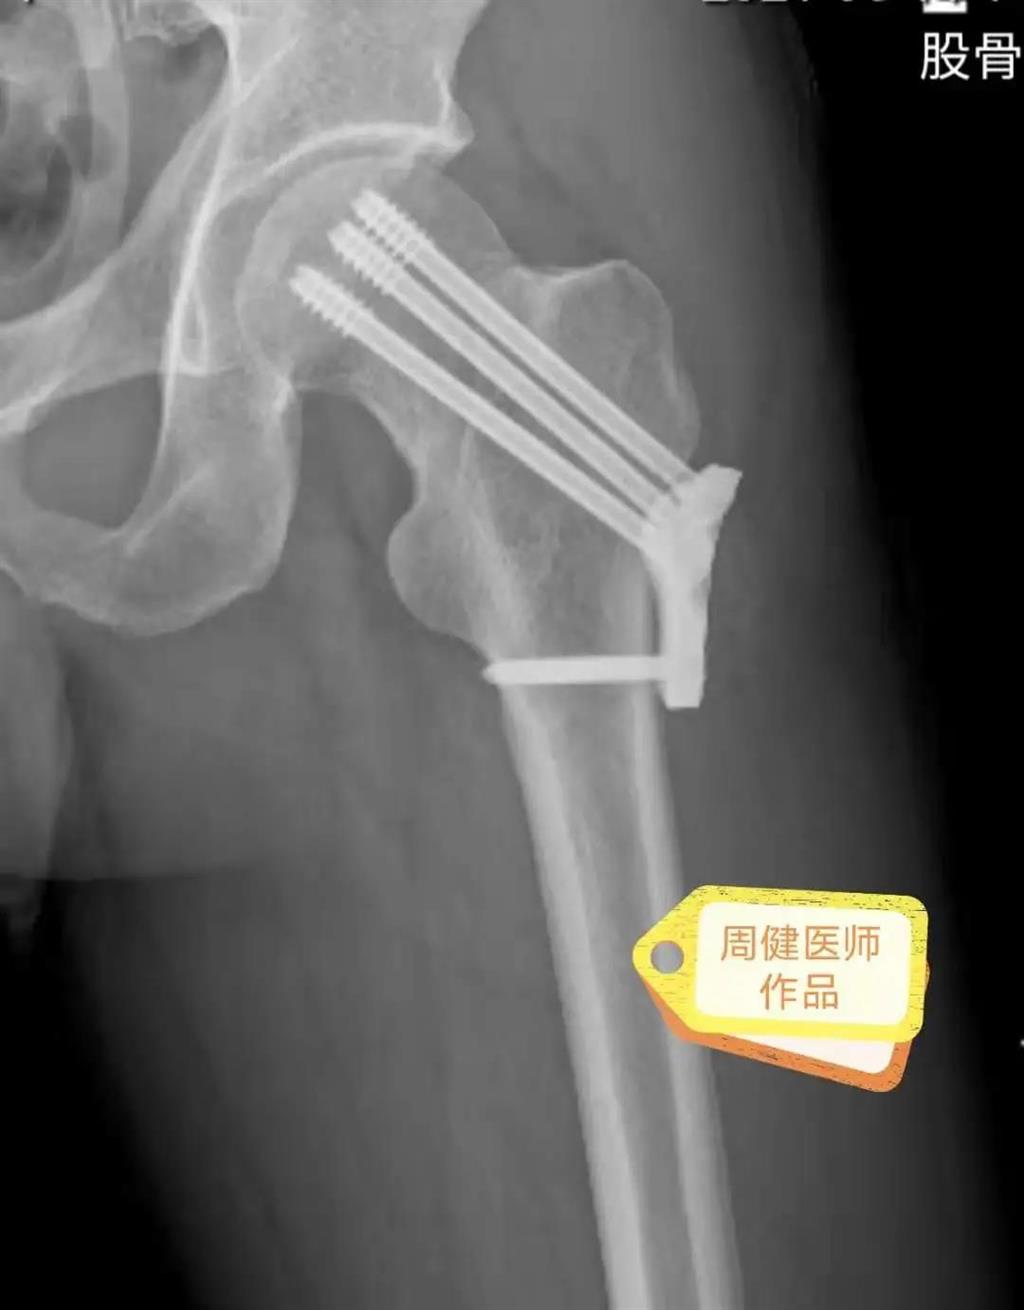

6月30日的“關(guān)節(jié)置換術(shù)”,患者是一位上了年紀(jì)的老人,苦于病痛折磨多年的他四處“求醫(yī)問藥”,最后在多位專家醫(yī)師及病友地力薦下選擇了和平國(guó)際醫(yī)院,在醫(yī)師團(tuán)隊(duì)“偷天換日”般的手術(shù)后,老人成功告別了苦纏多年的病痛。

周健說,這場(chǎng)“關(guān)節(jié)置換術(shù)”對(duì)于他們團(tuán)隊(duì)而言其實(shí)算是比較普通的手術(shù),因?yàn)樽鲞^很多同類的手術(shù),成功案例繁多,因此在手術(shù)操作上有較多地實(shí)操經(jīng)驗(yàn)。“不過話雖如此,作為醫(yī)生我們對(duì)于每一場(chǎng)手術(shù)都會(huì)全力以赴,這是為醫(yī)者的職責(zé)也是義務(wù)。”